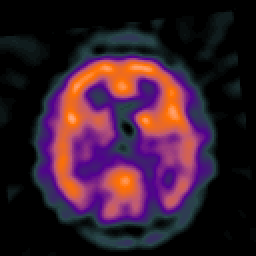

Alzheimer's disease: overlay -- Slice #33

[Home][Help][Clinical] Slice 33